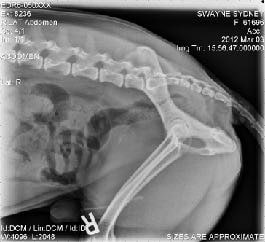

Cystotomy Entity page V2

Cystotomies